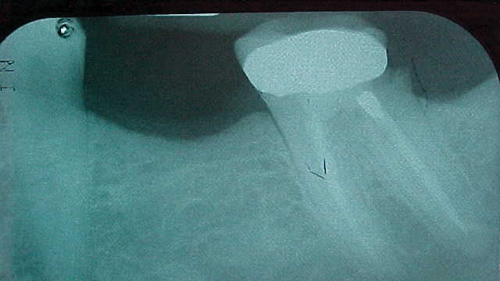

Figure 1: Grossly undercontoured crown margin

Your analogy about the crown margin made me laugh. I remember having a new patient in my chair with the worst crown margin I had ever seen. The x-ray showed the crown margin was undercontoured and the tooth was sticking out on the distal by a wide distance (figure 1). My boss exclaimed, “Man, you could hide a dead dog down in there!” I still laugh when I think of that.